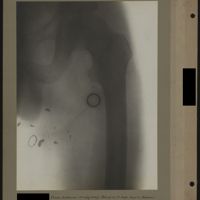

0062 - Page 58 - [Radiographie de la hanche]0062 - Page 58 - [Radiographie de la hanche]

0085 - Page 81 - [Radiographie de la hanche et du fémur]0085 - Page 81 - [Radiographie de la hanche et du fémur]

0087 - Page 83 - [Radiographies du fémur]0087 - Page 83 - [Radiographies du fémur]

0093 - Page 89 - [Radiographies du fémur]0093 - Page 89 - [Radiographies du fémur]